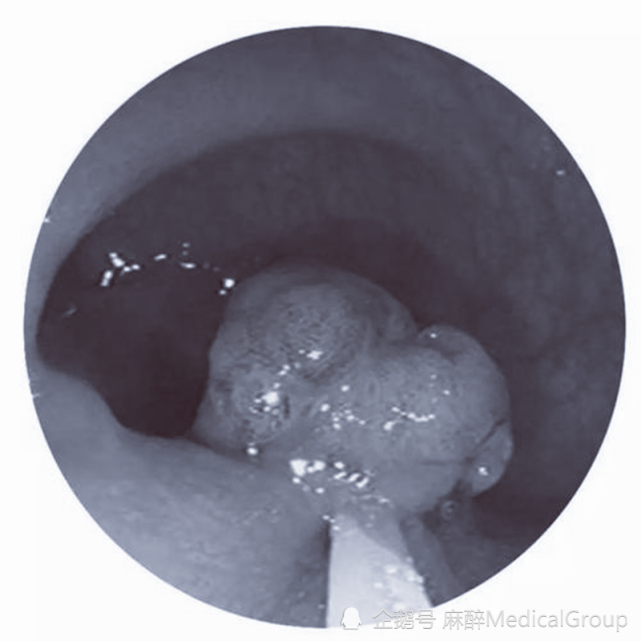

肠息肉是指肠黏膜表面突出的异常生长的组织,在没有确定病理性质前统称为息肉。其发生率随年龄增加而上升,男性多见。以结肠和直肠息肉为最多,小肠息肉较少。息肉主要分为是炎症性和腺瘤性两种。

还有一点是大家需要注意的,肠息肉的介绍里有“肠黏膜”这个字眼。其概念是,无论是肠道哪个部位、也无论是多大的息肉,只要它归属于“息肉”,就应该在肠黏膜上。